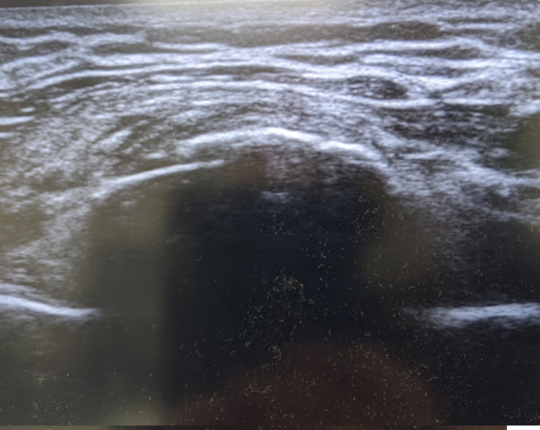

転倒してコンクリートに胸部を強打して受傷した方です。

肋骨骨折はレントゲンでは分かりにくい場合も多いですが、このようにエコーでは骨折部をはっきりと描出することが可能です。

長軸画像。骨折部が段差で描出されている。